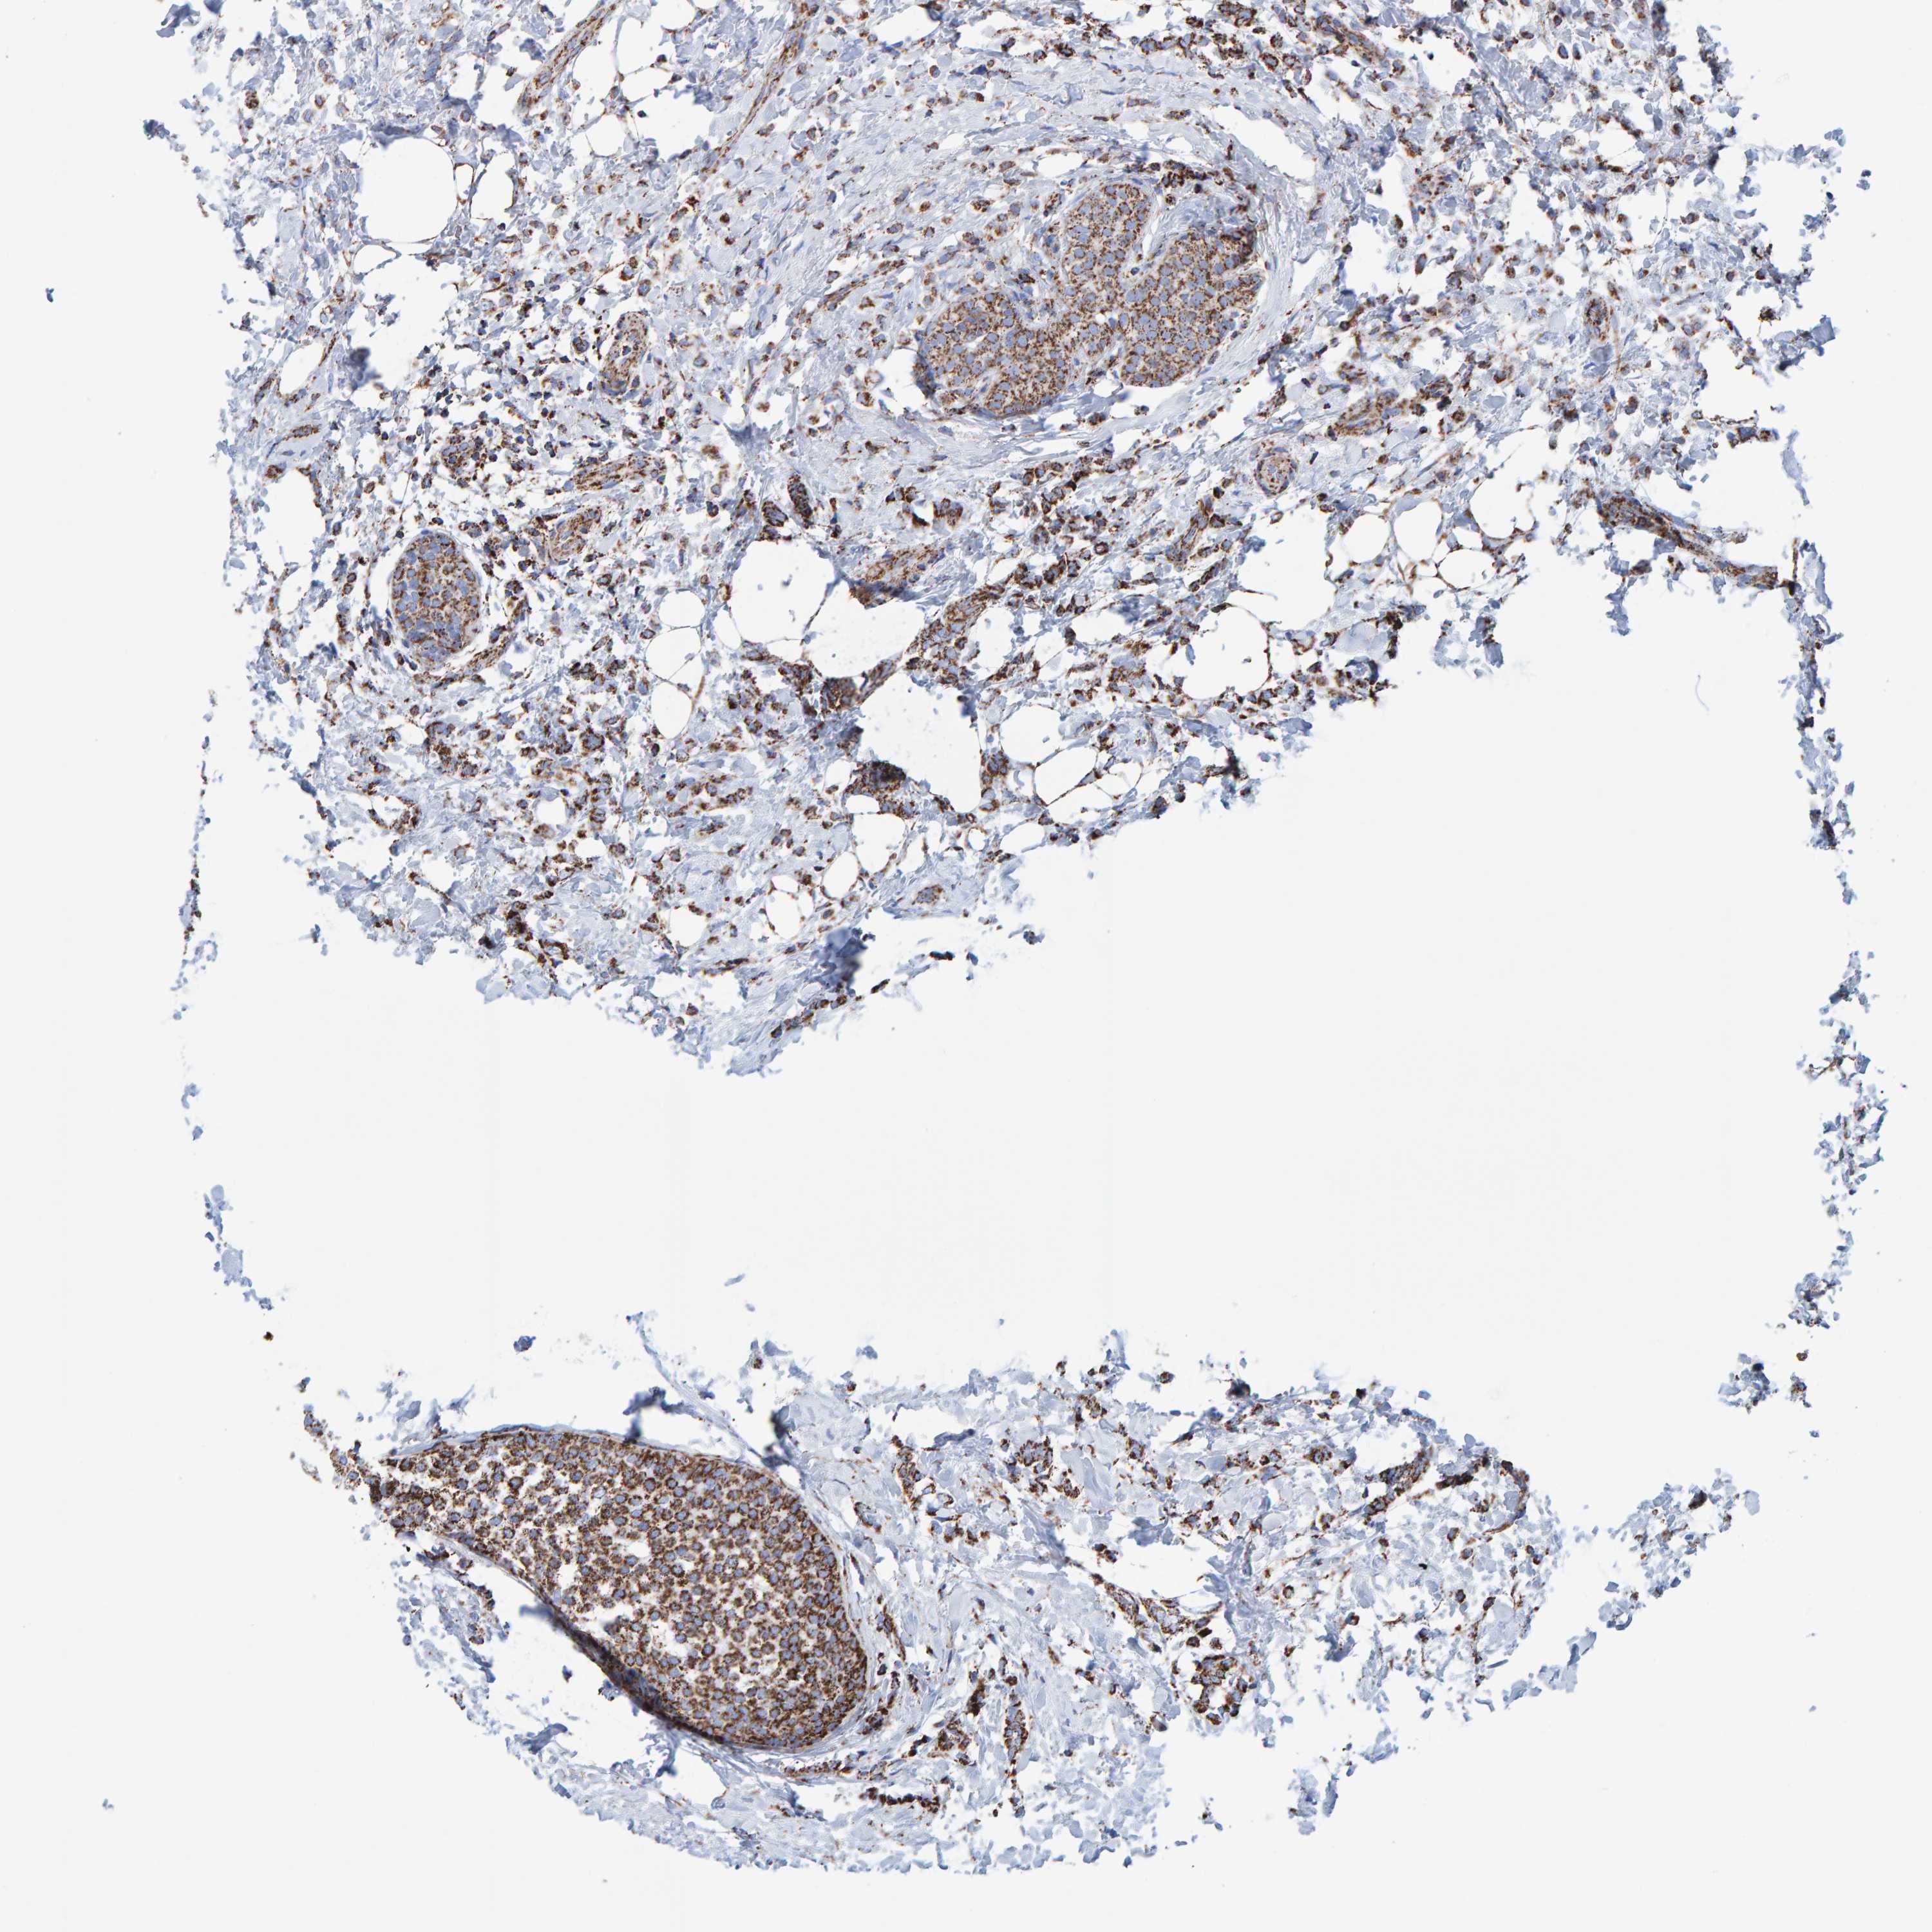

CANCER BREAST CANCER Show tissue menu

BRCA TCGA BRCA VALIDATION PROTEIN EXPRESSION